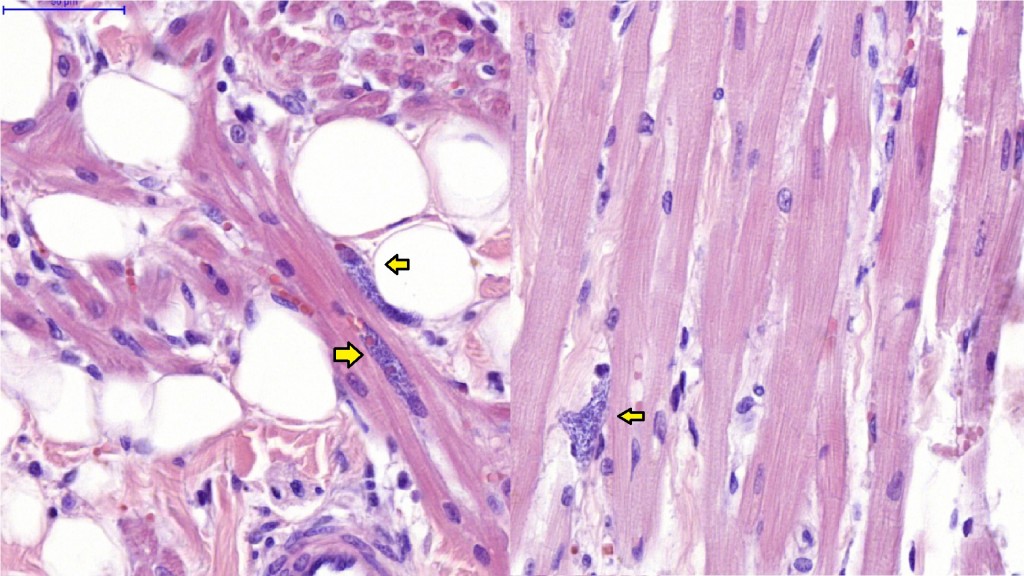

Межуточный миокардит: гистологические исследования

Раздел: Идеи и советы